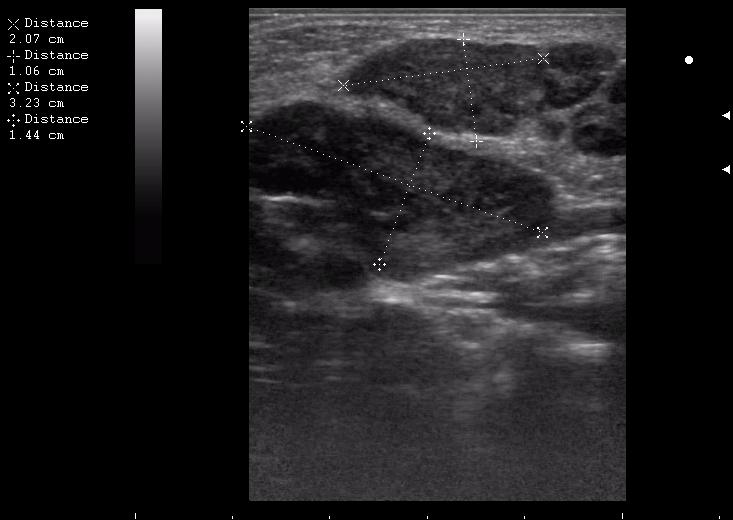

поднижнечелюстная слева